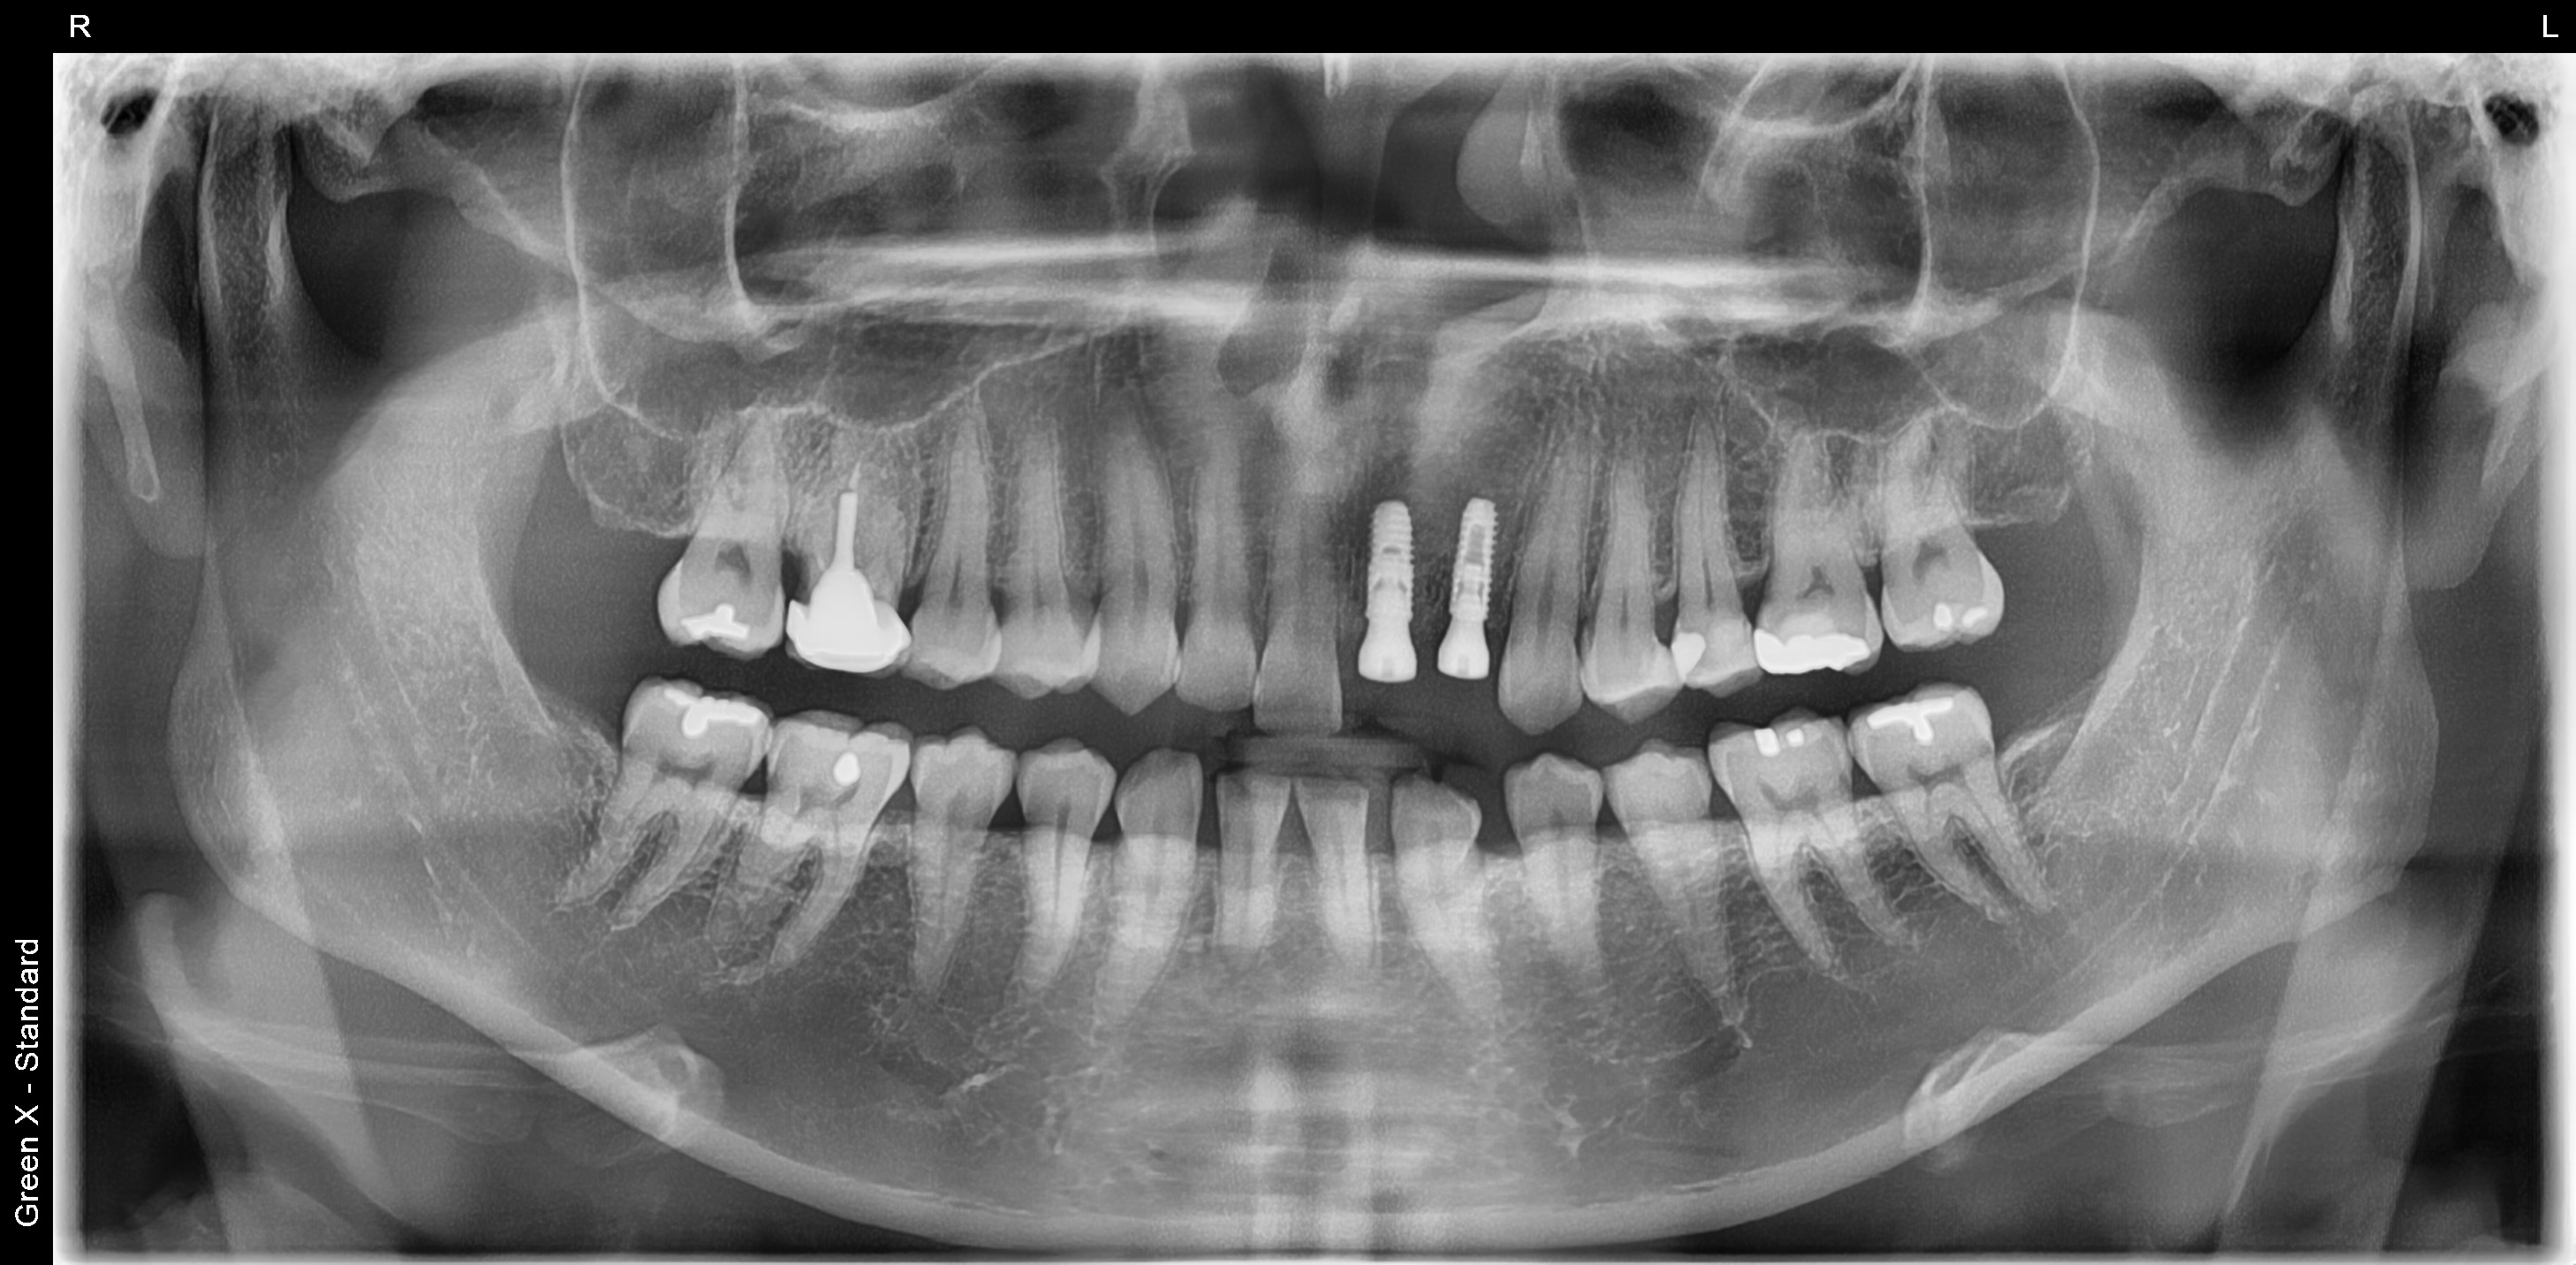

엑스레이 사진을 찍어보니 앞니 2개의 뿌리에 염증이 심하여 발치 당일 잇몸뼈 보존을 위하여 치조골 이식술을 먼저 진행하였습니다.

3개월 이후 잇몸뼈가 재생이된 것을 확인하고 임플란트 식립를 식립하였습니다.